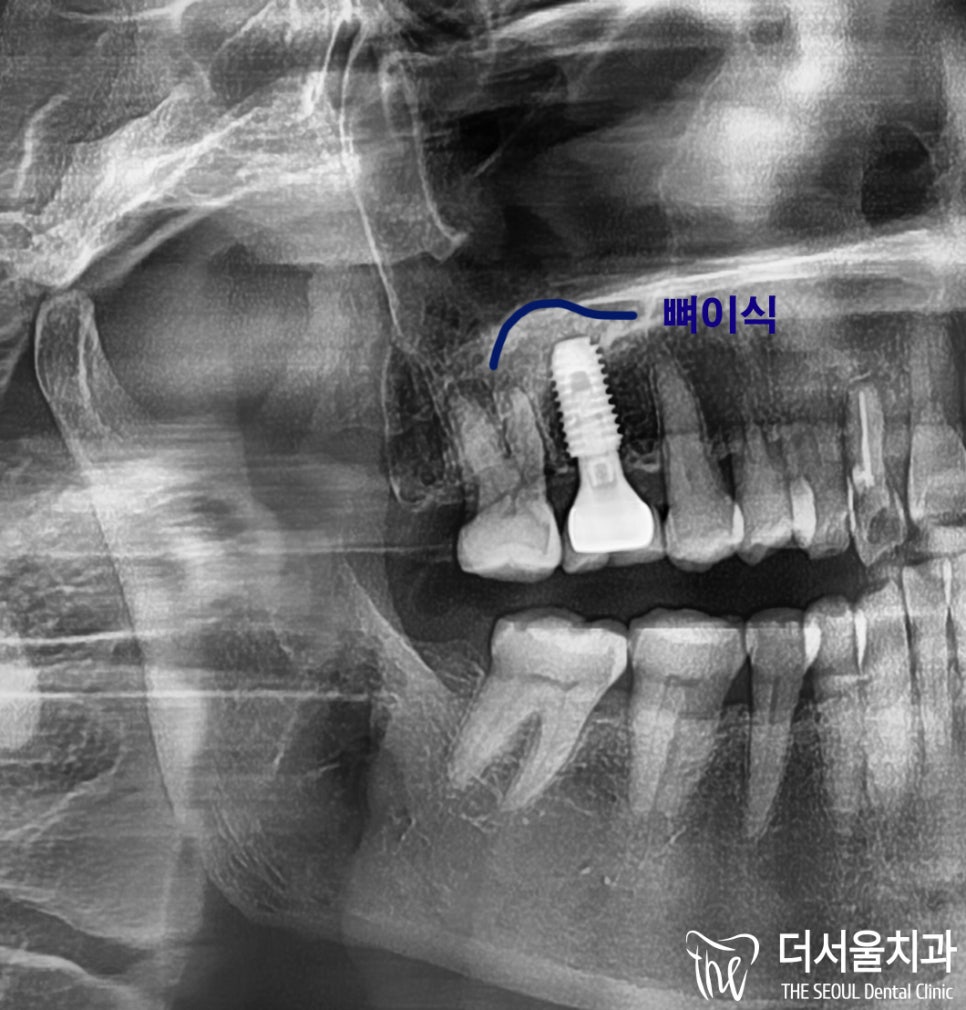

이대로 심으면

공기주머니가 뚫려버리기 때문에

상악동 거상술 후 뼈이식을 함께 진행했습니다.

공기주머니 올리는 수술

: 상악동 거상술도 완벽하게 잘 되었고

(뼈이식 완전 잘됨ㅎㅎ)